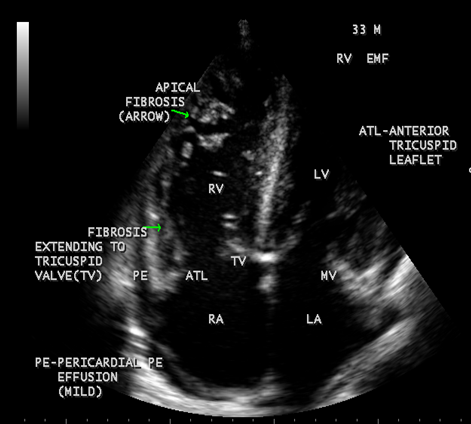

Figure 30: showing thick fibrous strands in the right ventricle with mild pericardial effusion suggesting right ventricular endomyocardial fibrosis in a 33-year old male.

Figure 31: showing tricuspid regurgitation with thick fibrous strands in the Right ventricle in a 33-year old male in RV EMF.